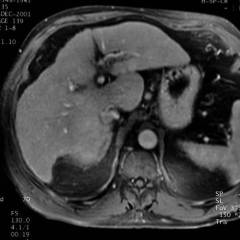

Cirrhose en poussée aigue. Le foie a un aspect globuleux. Après injection de gadolinium le rehaussement est hétérogène avec des plages à contours flous qui s'omogénéisent en quelques minutes. La fibrose est difficile à bien identifier avec précision.